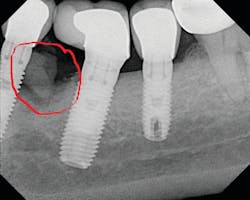

Detecting excess cement can usually be done with a radiograph if the cement is located in the interproximal region and is radiopaque (figure 4).